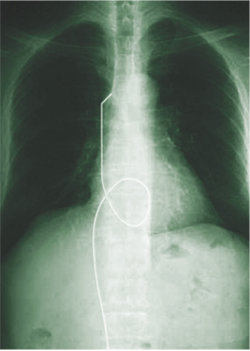

가슴 X선 사진에서 환자의 혈관 속에 들어 있는 철사가 흰 선으로 뚜렷하게 보인다. 사진 제공 권신애 변호사